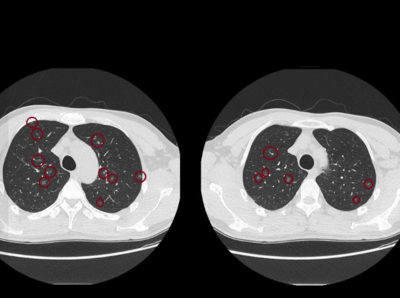

台中一名50歲男性,從事噴漆工作長達10年,另有20年的車床工作經歷;最近,他身體並無不適,只是進行例行性健檢,結果竟照出上百顆肺結節,連醫師也震驚。 《詳全文...》